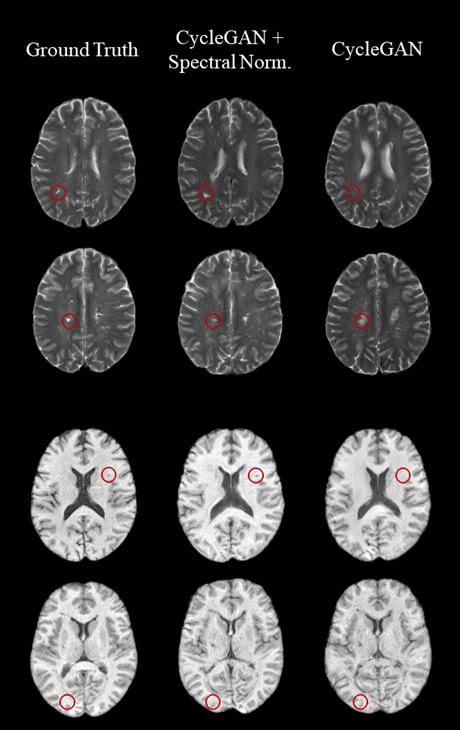

Overcoming the missing data challenge in clinical imaging using CycleGAN based on brain MRI in Multiple Sclerosis

This study evaluated CycleGAN models—with and without spectral normalization—for generating missing MRI sequences in MS, showing improved performance with spectral normalization, especially under inconsistent scan quality. This work was presented as a traditional poster at the ISMRM 2024 annual meeting.